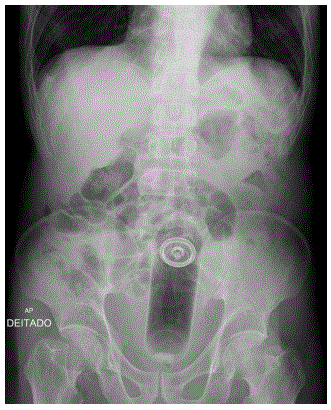

Paciente sexo masculino, 42 anos, procura serviço de emergência queixando-se de dificuldade para evacuar e eliminar gases há 2 dias, acompanhado de cólicas abdominais. Refere ter eliminado muco com laivos de sangue. Sem antecedentes mórbidos.

Ao exame físico: PA: 140 X 80 mmHg; Pulso: 90 bpm (rítmico e cheio).

FR: 14 ipm; Tax: 36,8º C.

Bom estado geral, corado, desidratado+, afebril e anictérico.

Tórax sem anormalidades ao exame.

Abdome: distendido+, flácido, doloroso à palpação com massa palpável no hipogástrio, descompressão brusca negativa. Ruídos hidroaéreos presentes.

Conduta:

• Hidratação com solução cristaloide

• Analgesia

• Solicitado exame de imagem (RX abdome) mostrado ao lado.

Qual é a abordagem mais indicada a ser realizada a seguir, com base nos dados clínicos e no exame de imagem?

enunciado 1542983-1